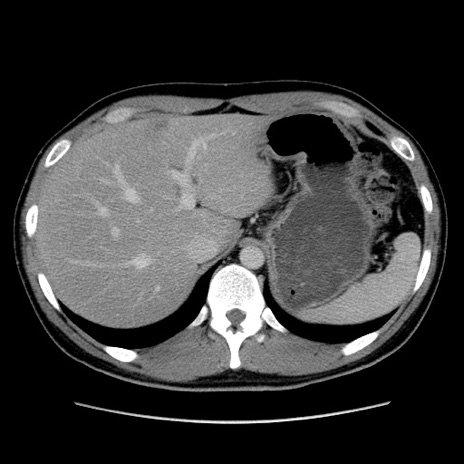

症例36(横断像)

【症例】20歳代 男性

【主訴】心窩部痛

【現病歴】今朝より上腹部痛あり。一旦軽快していたが再度出現したため救急要請。昨日夕に白身の魚を含む刺身を食べた。

【身体所見】BP 136/89mmHg、HR 74/min、BT 37.0℃、腹部:膨満、軟、心窩部に圧痛あり。反跳痛なし、筋性防御なし、腸雑音やや亢進あり。

【データ】WBC 17700、CRP 0.48